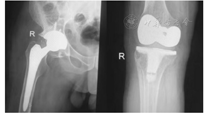

临床诊断为血友病性关节炎,双髋及双膝关节均有关节置换适应证,但右侧髋、膝关节病变较左侧严重,在完善相关检查,无心肺等手术禁忌证后,于全麻下行"右侧全髋关节置换术+右侧全膝关节置换术"。术前3 d静脉输注凝血Ⅷ因子2 000 IU/次,每12小时输注1次;术前2 h静脉输注凝血Ⅷ因子3 000 IU,术前30 min急查PT13.8 s,APTT 31.3 s,凝血Ⅷ因子活性(FⅧ:C)108.6%;术前30 min静脉输注联合术中局部应用氨甲环酸减少出血及输血,术中动态监测凝血Ⅷ因子活性保持在80%以上,术中出血900 ml,输全血600 ml。术后持续监测凝血Ⅷ因子活性,按需输注凝血Ⅷ因子,同时给予抗感染、止血、止痛等对症治疗。术后第32天影像学检查提示右侧人工髋、膝关节位置正常,关节对位良好,结构完整。手术前后影像学检查见图1、图2。术后第34天出院。

6.功能康复锻炼。术后功能康复锻炼是关节置换治疗血友病性关节炎的重要组成部分,是改善关节功能、提高生命质量的重要途径[24],由于血友病患者常常关节周围肌肉挛缩、关节畸形,功能康复锻炼难度大[25],功能康复锻炼须在康复师的指导下进行,并遵循个性化和循序渐进的原则[7]。对于无抑制物的血友病A型血友病性关节炎患者术后功能锻炼的时机,专家共识[7]推荐在术后24 h开始,锻炼应在凝血因子替代治疗保护下进行,高娜等[26]认为输注凝血因子后6 h内凝血因子活性在40%以上,这一阶段是功能锻炼的安全期,据此我们制订了个性化的三阶段康复锻炼计划。(1)早期训练(术当日):手术当日患者麻醉完全消退后为患者按摩股四头肌和腓肠肌,指导患者活动双侧足趾及踝关节,并抬臀每2小时1次;术后6 h抬高床头,指导患者行踝泵运动,以及深呼吸、咳嗽训练。(2)中期训练(手术次日至1周):术后次日晨查凝血Ⅷ因子活性(FⅧ:C)为116.5%,继续上述训练,膝部引流管拔除后指导行患肢股四头肌等长收缩训练,健肢等张收缩训练等肌力训练,上述训练项目10次/组,10组/d,通过训练促进血液循环,预防静脉血栓的形成,同时可避免肌肉萎缩,利于关节功能恢复;术后48 h髋部引流管拔除后指导继续上述训练的同时行臀肌等长收缩训练,10次/组,10组/d,利于预防肌肉萎缩;术后第4天晨查凝血Ⅷ因子活性(FⅧ:C)为91.6%。指导患者在床上做髋、膝关节主动屈伸锻炼,并按摩下肢肌肉3~4次/d,目的是提高肌力,为离床活动及负重奠定基础;术后5 d开始指导患者进行上下床、离床坐及站立等体位转移练习。离床坐30 min后扶助行器辅助站立3 min,患者感觉无头晕、恶心,扶助行器在病房内缓步行走5 m,此后逐渐延长离床坐、站立时间,加大行走距离。(3)后期训练(术后第2周开始):持续监测凝血Ⅷ因子活性在45%~65%。继续股四头肌、踝泵及髋膝关节的主动屈曲训练,重点进行助行器辅助站立、拄拐行走及步态训练。在康复师的指导下,经过上述三阶段康复锻炼,患者术后18 d时能独立坐起,可扶助行器下床活动;术后第32天影像学检查人工髋、膝关节位置良好,于术后第34天出院。

经采取科学、规范的围手术期护理,本例患者切口Ⅰ期愈合,未发生下肢静脉血栓、人工关节脱位及松动等并发症,术后第18天可扶助行器下床活动,术后第34天出院,出院前影像学检查髋、膝关节假体位置及力线满意,出院后2个月随访右下肢功能恢复良好。人工关节置换可有效缓解血友病性关节炎患者的疼痛,改善关节功能,但同期行髋、膝双关节置换手术创伤大、风险高,增加了围手术期护理难度。凝血因子替代治疗是进行手术和术后康复的必要条件,是整个围手术期护理的重点。术后要加强病情观察,住院期间积极采取措施预防切口感染、导管滑脱、下肢深静脉血栓、假体脱落及松动等并发症的发生,在疼痛耐受和安全的凝血因子活性条件下指导患者积极进行科学的功能康复锻炼。出院后要定期回访,根据患者康复情况进行健康指导,最大限度的提高患者生命质量。